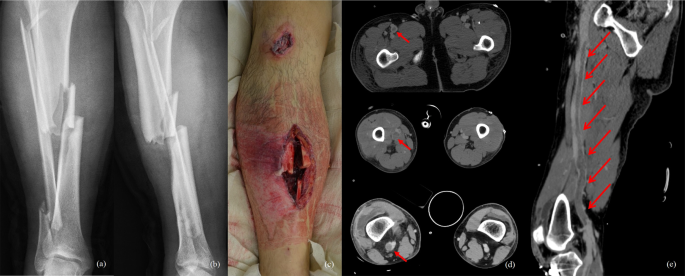

Patients were not routinely screened for VTE, and only those with symptoms or signs suggestive of VTE were assessed for definitive diagnosis. Clinical signs suggestive of symptomatic DVT, including pain and marked swelling of the corresponding calf or thigh, tenderness on indurated venous segment, Homan’s sign, variable skin discoloration of the lower extremity, and prominence of superficial veins were evaluated daily36. PE, defined as symptomatic when a patient had symptoms such as dyspnoea, tachypnoea, chest pain, and cough, was suspected with sudden hypoxia (O2 saturation <95%) or hypoxemia (PaO2 < 83 mmHg)37. To detect VTE, 64-channel multidetector computed tomography (Brilliance 64®, Philips, Eindhoven, the Netherlands) was performed (Fig. 2).

A 41-year-old male patient with right tibio-fibular open fracture and left ankle fracture after a motorcycle accident developed right lower-extremity severe swelling and pain during passive ankle and toe motion (a–c). CT angiography was performed. A massive thrombus in the right common femoral vein and calf were confirmed (red arrow) and chemical treatment was administered continuously (d,e).